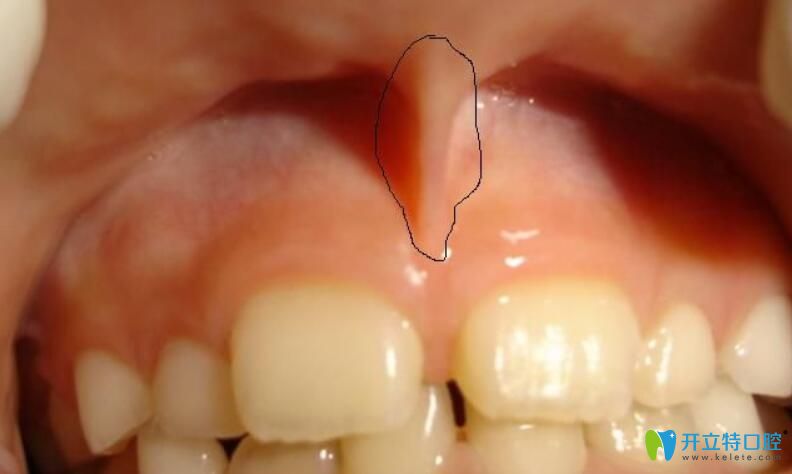

14、唇系帶異常

唇系帶附著于上排中間兩顆門牙之間的外側(cè)牙齦和牙槽粘膜之間,如果隨著年齡增長,孩子的系帶沒有隨之退縮,就會導(dǎo)致上門牙之間出現(xiàn)較大的縫隙。

唇系帶異常